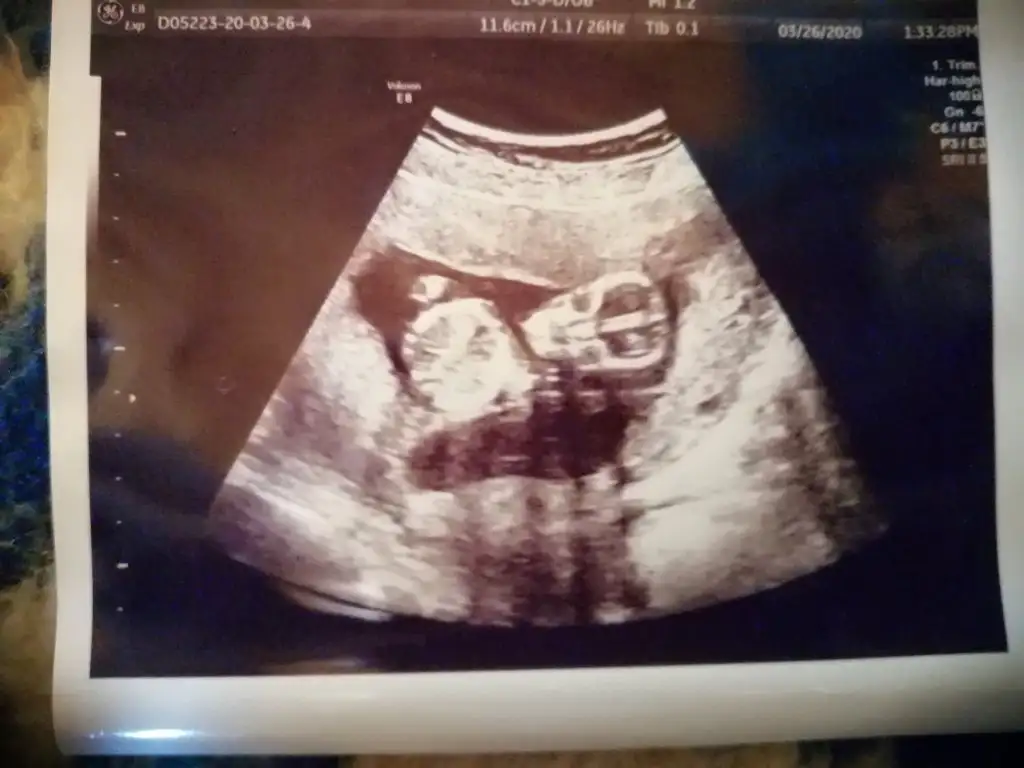

Bugün kontrole gittim doktor bacaklarını açmıyor cinsiyet göremedim dedim ikra meyra sen erkek demistin hep ama bitek bu foto var 14 haftalik bu arada yine varmi tahmin

ay bende çok merak ediyorum 14haftalık usg bu acaba kız mı erkek mi olacak 😊 doktor bacaklarını açmıyor dedi 2 hafta sonrada çağırdı kesin Konuşuruz dedi ama ben duramıyorum meraktan

Nubu net değil sanki erkek gibi bilemedim ben 11 12 13 haftalara bakıyorum 14 de organı oluşuyor çunki